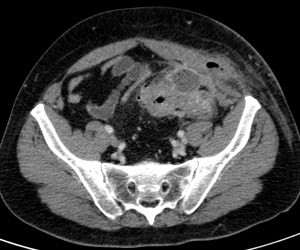

Se completa el estudio con TC de abdomen con contraste i.v.

TC ABDOMEN: Se confirman los hallazgos vistos en ecografía. Se aprecia un engrosamiento mural > 4mm de un segmento aproximado de 5.5 cm de longitud con infiltración de la grasa adyacente y sin visualizar colecciones ni gas extraluminal, hallazgos compatibles con diverticulitis aguda no complicada.

CONCLUSIÓN: Diverticulitis aguda no complicada. HINCHEY grado 0